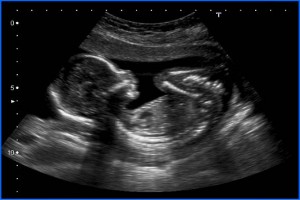

Diplomados en Ultrasonografía

Hola, conoce nuestros diplomados.